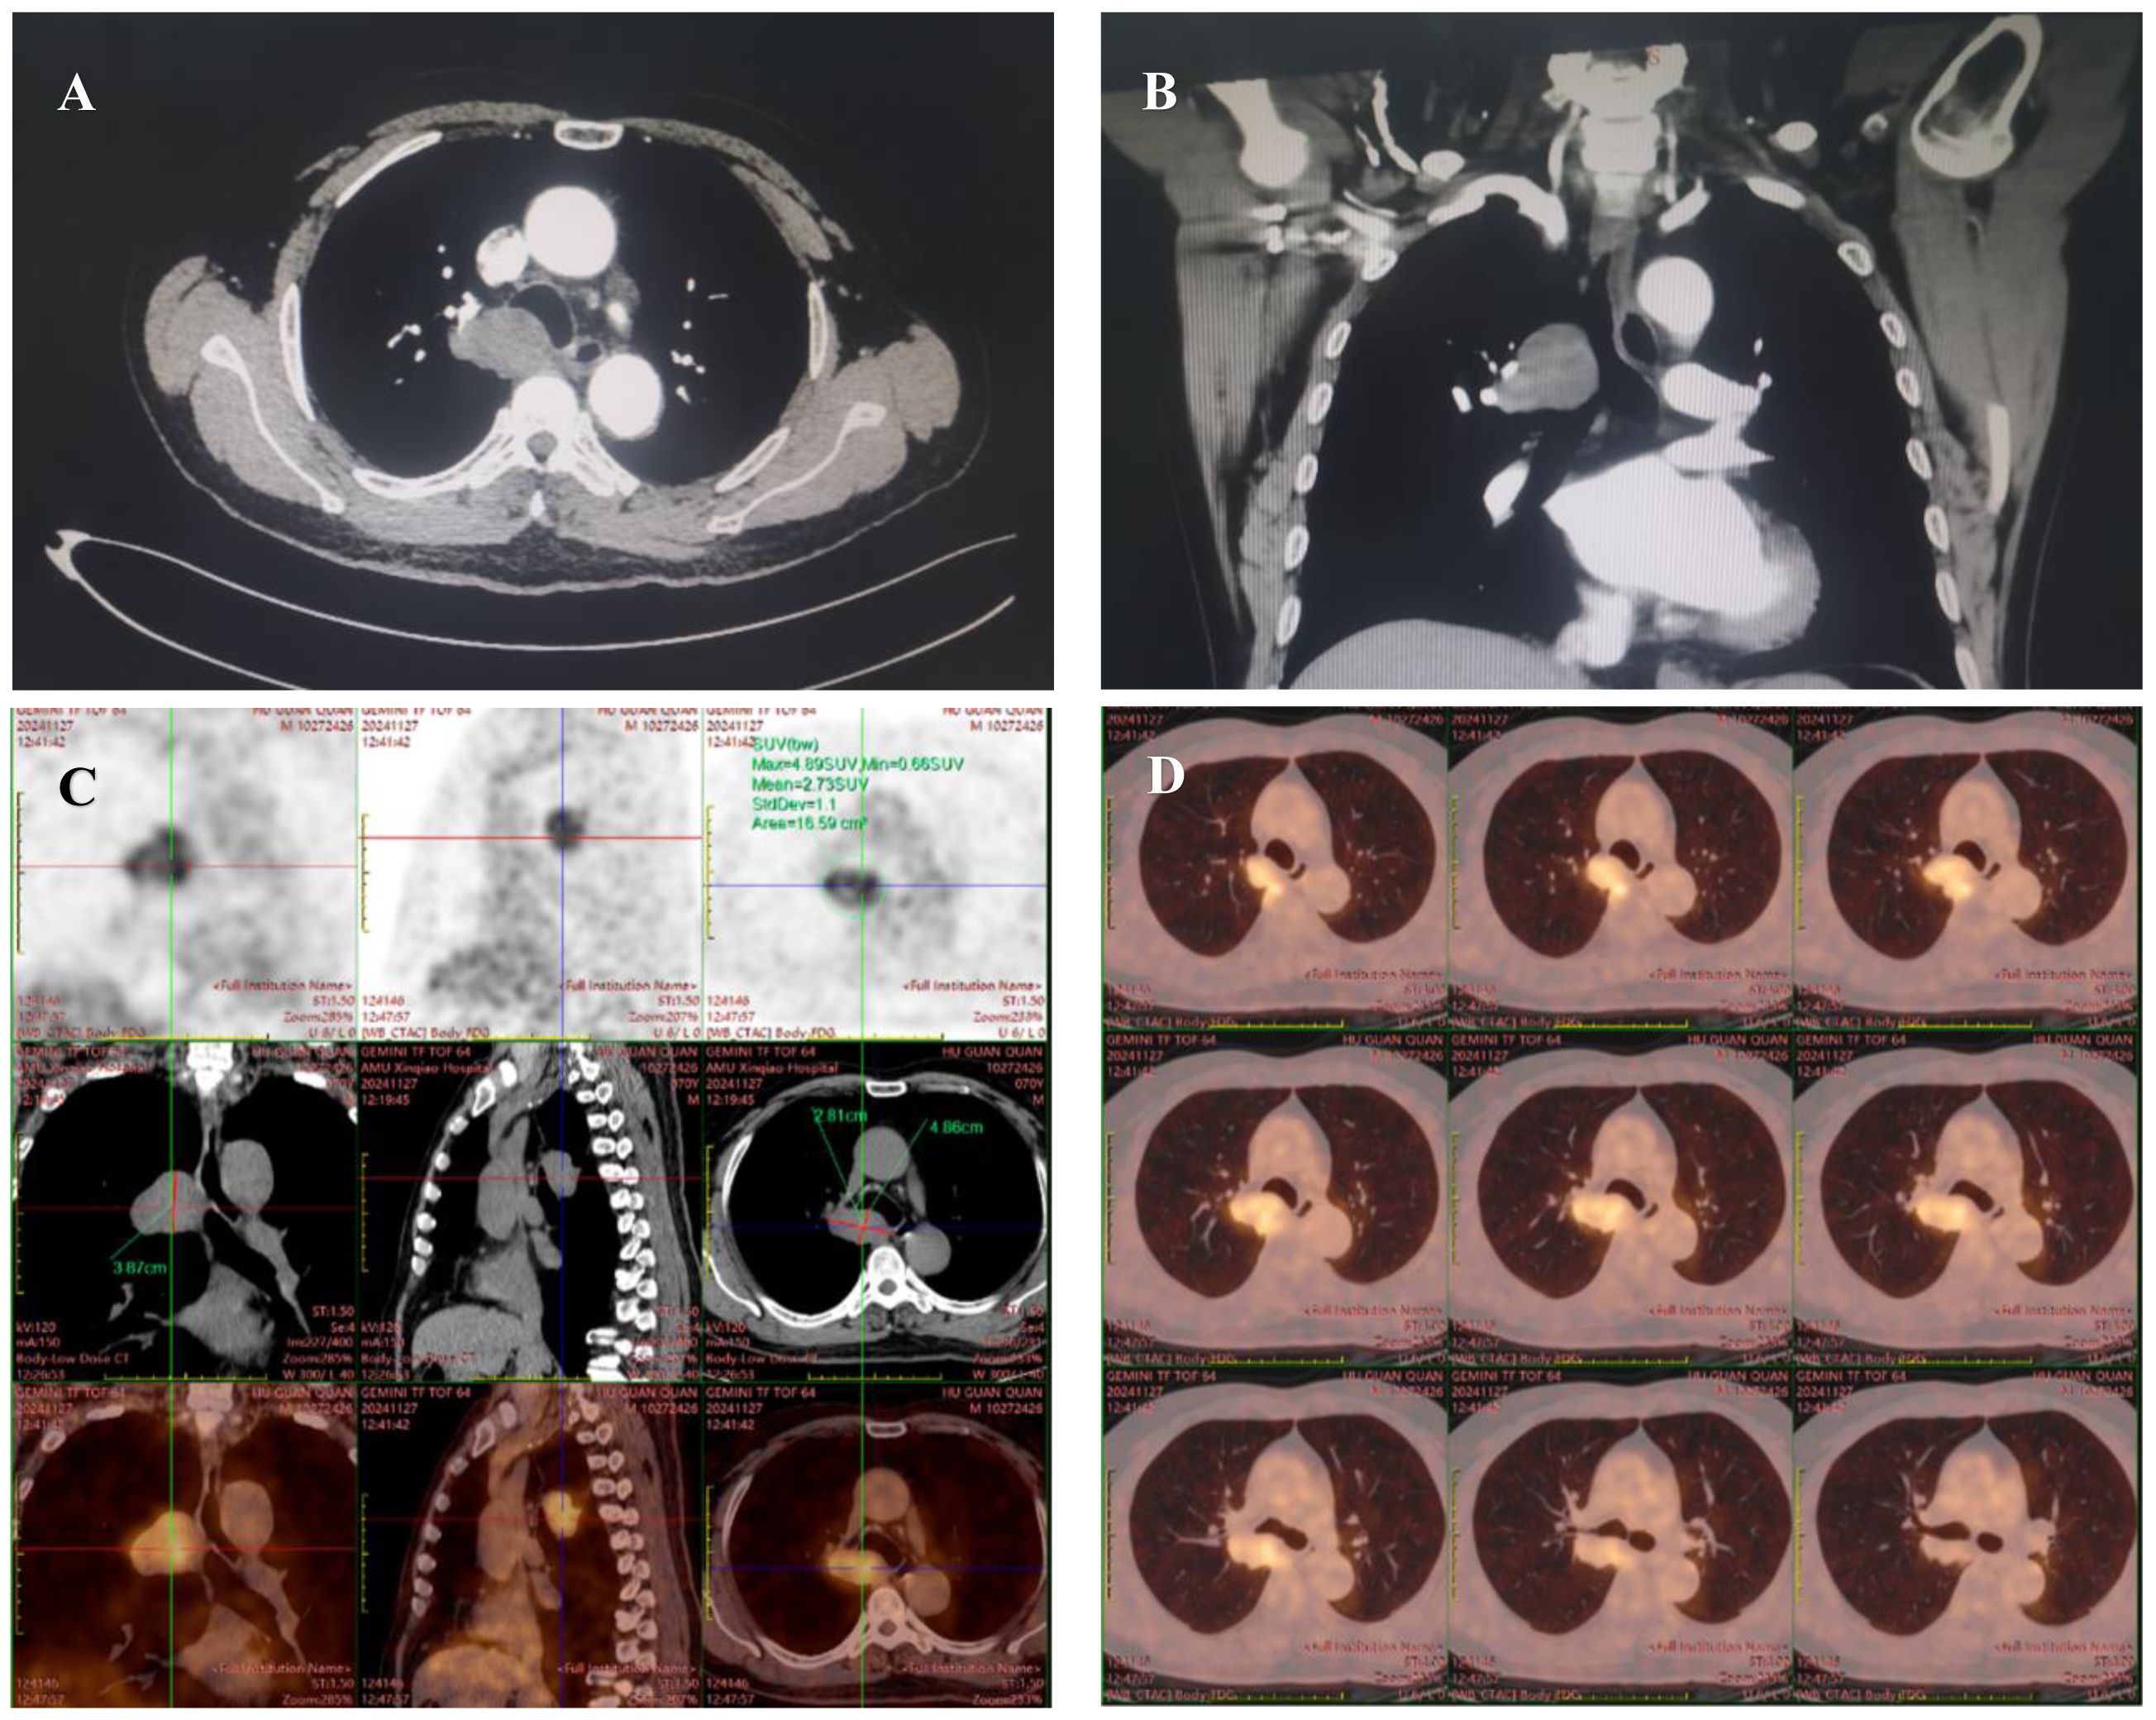

A 70-year-old male patient with no known comorbidities or history of smoking or alcohol abuse was referred to our department for surgical evaluation of a mass in the upper-right part of the tracheal carina that was incidentally detected on thoracic computed tomography during a routine health check-up. Enhanced chest CT scanning revealed a circular and homogeneous mass measuring 5.1 x 3.5 cm in the middle mediastinum adjacent to the hilar region of the right lung, demonstrating heterogeneous and gradual enhancement. The mass was closely associated with the right wall of the lower tracheal segment and the right main bronchus felt to represent a tracheal tumor. The upper pole of the tumor was 3 cm above carina level and the azygos vein was compressed (Figures 1A, B). A fluorodeoxyglucose F18 positron emission tomography (PET) scan showed abnormal uptake in the mass (maximum standardized uptake value [SUVmax]: 4.9), suggesting a malignant tumor, while no distant metastasis was identified (Figures 1C, D). To assess the spatial relationship of the tumor relative to the esophageal wall, endoscopic ultrasound (EUS) was employed. And the result revealed hypoechoic lesions external to the wall of the mid-esophagus, characterized by irregular margins and heterogeneous internal echoes, yet the layers of the esophageal wall remained distinctly demarcated and intact. Bronchoscopy was performed, revealing an extramural compression covered by normal mucosa in the membranous portion of the lower trachea, located just above the carina. Endobronchial ultrasound-guided transbronchial needle aspiration (EBUS-TBNA) results showed a spindle cell neoplasm of smooth muscle cell origin; however, a definitive diagnosis could not be established based on these findings alone.

Figure 1. Chest computed tomography scan (A, B) reveals a 5.1 x 3.5 cm mass closely abutting the right wall of the lower tracheal segment and the right main bronchus. An 18F-FDG PET/CT scan (C, D), extending from the vertex of the skull to the upper thighs for preoperative evaluation, revealed fluorodeoxyglucose accumulation in the tumor (maximum standardized uptake value, 4.9), suggesting a suspected malignancy.